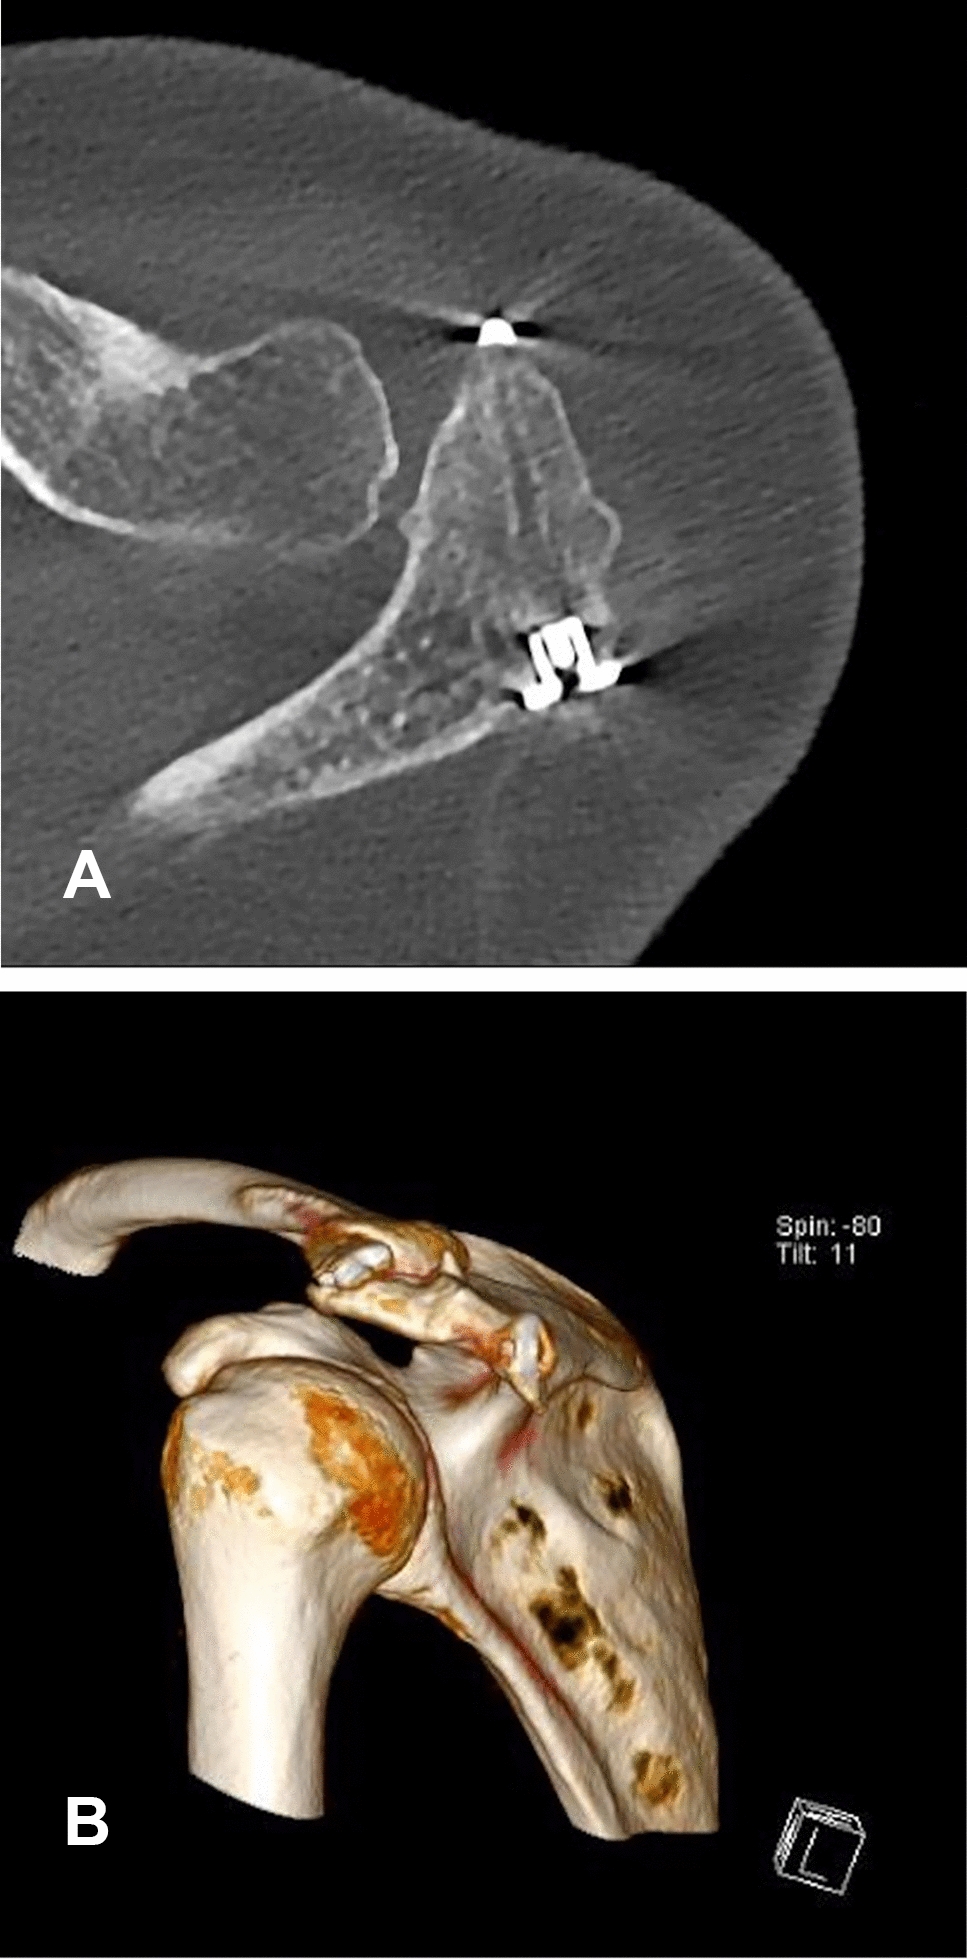

Postoperative rehabilitation involved initial shoulder immobilization in a Donjoy® Ultrasling® (DJO Global) for 8 weeks accompanied by physiotherapy and analgesia. One year after surgery, the persisting consolidation of the os acromiale and the proper position of the implant were confirmed by radiographs and computer tomography imaging (Figs. 4 and 5). The patient remained pain free and the hardware was not palpable. No noticeable discomfort around the implants was experienced. The assessment of the subjective shoulder value (SSV) showed 90%. The shoulder range of motion improved to 180° flexion, 170° abduction and 50° external rotation.

Fig. 5

AB Computer tomography control scan at the 12-month follow-up showing persisting consolidation of the os acromiale and good implant position